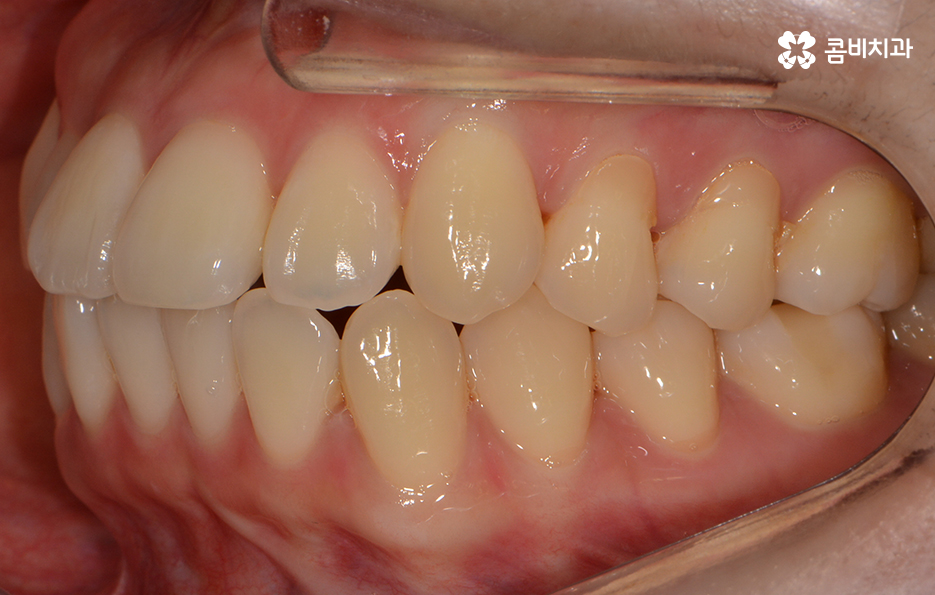

발치가 진행되었고 콤비교정 장치를 사용하여 교정이 진행된 사례

콤비교정이 마무리된 후 장치를 풀어낸 모습

교정 장치를 풀어낸 후 유지 장치를 부착한 상태